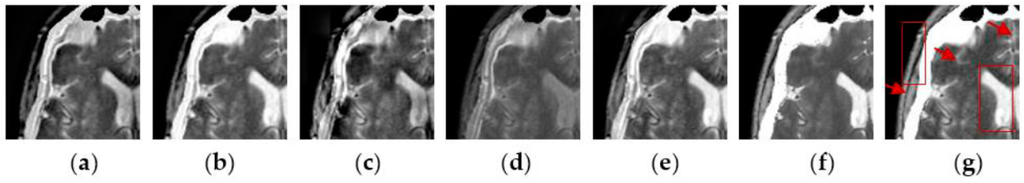

4.2. Visual Comparisons of Fused Results